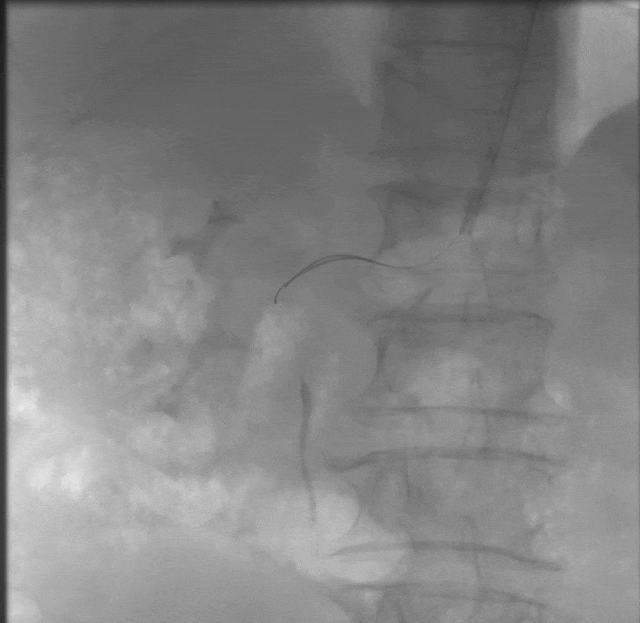

外院造影:

右肾动脉重度狭窄

2.导管配合0.035导丝进入腹主动脉下端,造影示:腹主动脉走形迂曲,血流通畅,右肾动脉主干起始段重度狭窄>90%,远端及分支显影浅淡。